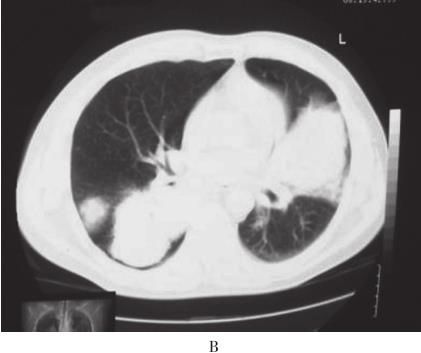

患者,男,56岁,因“活动后气短4年,加重3周”于2010年10月12日入院。入院前4年无诱因出现活动后气短,吸气时明显。3年前当地医院胸部CT检查示:双肺野内多个大小不等团片状密度增高影(图1A、B)。支气管镜下见:左上叶开口、右上叶开口及右下叶基底段开口处黏膜充血肿胀,管腔狭窄。支气管镜活检病理显示有大量淋巴细胞浸润。抗感染治疗后症状稍缓解。入院前1年上述症状加重,胸部CT示:双肺多发结节状、团块状病灶(图1C、D)。CT引导下肺穿刺活检病理示有大量淋巴细胞及浆细胞浸润,血管扩张充血,炎性渗出。诊断为双肺多发炎性肉芽肿,具体治疗不详。入院前2个月出现反复右侧鼻腔少量出血。入院前3周活动后气短加重,拟诊“双肺多发阴影性质待查”收入院。病来无发热、盗汗、咯血、胸痛、皮疹、关节痛。患者4年间多次在当地医院就诊,“怀疑肺结核、肺真菌病及肉芽肿病”,经验采用抗结核、抗真菌等治疗,具体治疗方案及疗程患者及家属叙述不清,疗效不佳。入院前半年,出现乏力、食欲下降,体重减轻4~5kg。

图1 胸部CT

A、B:2007年4月胸部CT示双肺野内多个大小不等团片状高密度.C、D:2009年10月胸部CT示双肺多发结节样、团块样病.E~G:2010年10月胸部CT示右肺下叶巨大团块状类软组织密度影,双肺弥漫性团片状浸润及实变影,纵隔内多发肿大淋巴结;胸片示右下肺团块影,双肺多发结节影